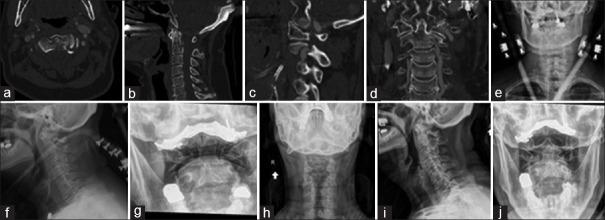

A total of 54 patients were included for analysis. The average time spent in a halo vest was 2.69 (0.58) months, and the average time to final follow-up was 5.49 (5.84) months. The most common fracture morphologies were the Hangman variant (29.6%) and type III odontoid (29.6%). Forty-nine patients (94.2%) out of 52 patients considered were successfully treated as defined by the lack of need for surgical intervention. Three patients (5.6%) experienced medical complications; two of the three patients died within 30 days of HVI. Lastly, 18 patients (33.3%) experienced HVI instrumentation-related complications, the most common of which was loose halo pins (13.0%).

共纳入54例患者进行分析。头环背心的平均佩戴时间为2.69(0.58)个月,末次随访的平均时间为5.49(5.84)个月。最常见的骨折形态是绞刑架型(29.6%)和Ⅲ型齿状突骨折(29.6%)。在52例被评估的患者中,49例(94.2%)按照无需手术干预的定义被成功治疗。3例患者(5.6%)出现医疗并发症;其中2例在HVI术后30天内死亡。最后,18例患者(33.3%)出现与HVI器械相关的并发症,最常见的是头环针松动(13.0%)。